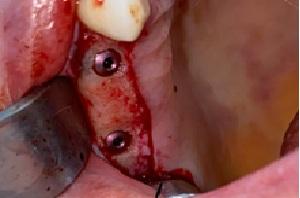

The placement of a dental implant requires a screw and an abutment.

These elements are at the core of the implant system and bridge the gap between the crown and the bone.

Once the implant is placed, it needs to be left in the bone for the duration of osseointegration. During this process, the bone heals around the implant and encapsulates it as the body does not recognize it as a foreign object. Due to osseointegration, the placement of a complete implant with its crown requires two separate appointments spaced several months apart.